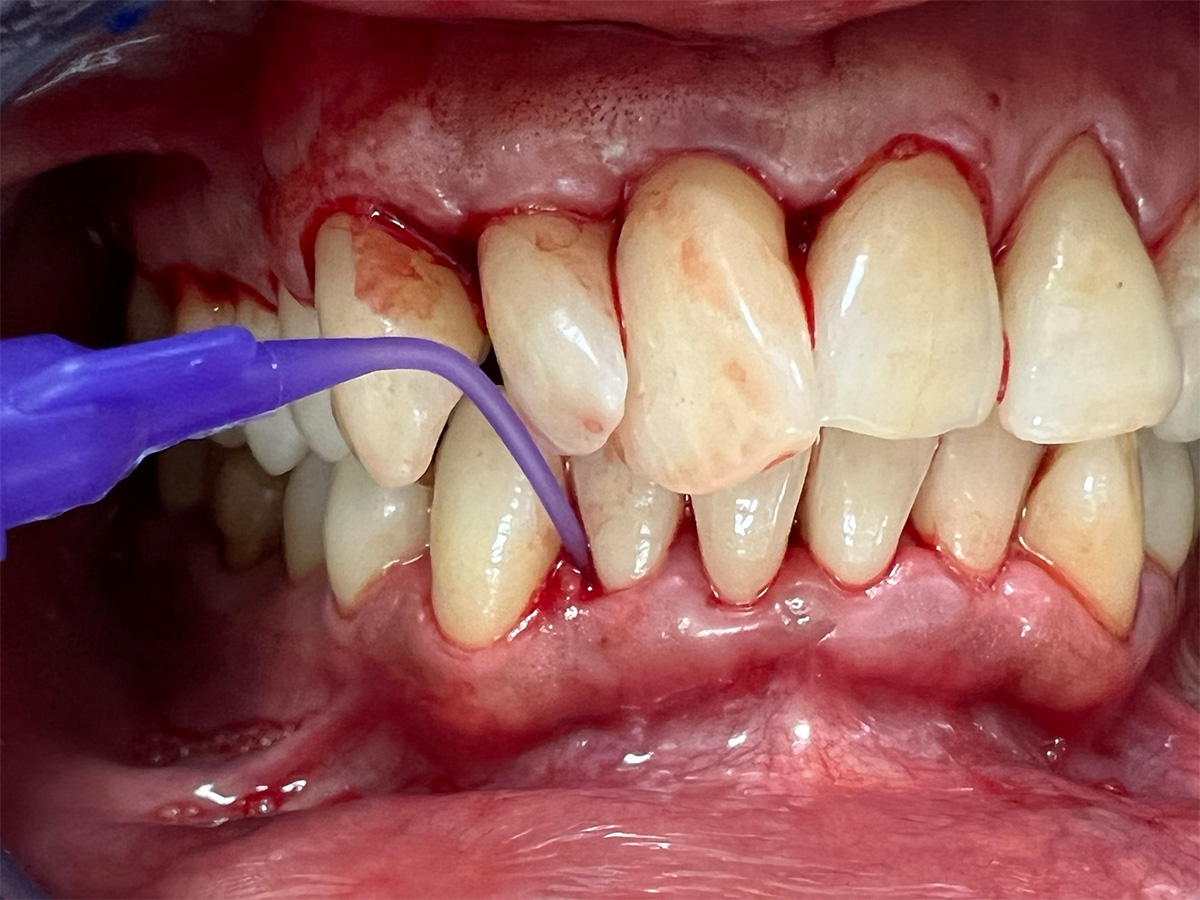

• Parodontale Krankheitsbilder erkennen

HANDS-ON

Praktische Übungen am Phantomkopf / Modelle / Schweinekiefer